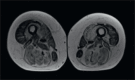

Tripartite motif-containing protein 32 (TRIM32) is a member of the TRIM ubiquitin E3 ligases which ubiquitinates different substrates in muscle including sarcomeric proteins. Mutations in TRIM32 are associated with Limb-Girdle Muscular Dystrophy 2H. In a 66 old woman with disto-proximal myopathy, we identified a novel homozygous mutation of TRIM32 gene c.1781G > A (p. Ser594Asn) localised in the c-terminus NHL domain. Mutations of this domain have been also associated to Sarcotubular Myopathy (STM), a form of distal myopathy with peculiar features in muscle biopsy, now considered in the spectrum of LGMD2H. Muscle biopsy revealed severe abnormalities of the myofibrillar network with core like areas, lobulated fibres, whorled fibres and multiple vacuoles. Desmin and Myotilin stainings also pointed to accumulation as in Myofibrillar Myopathy. This report further confirms that STM and LGMD2H represent the same disorder and suggests to consider TRIM32 mutations in the genetic diagnosis of Sarcotubular Myopathy and Myofibrillar Myopathy.